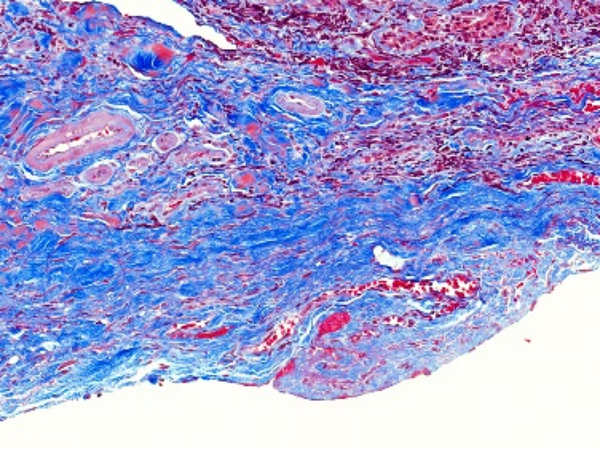

MASSON染色利用不同染料分子與組織結(jié)構(gòu)的相互作用,實現(xiàn)對膠原纖維和肌纖維的精準(zhǔn)區(qū)分。在染色過程中,肌纖維呈現(xiàn)為紅色,而膠原纖維則呈現(xiàn)為綠色或藍(lán)色。這種色彩對比使得纖維組織在顯微鏡下變得清晰可見,醫(yī)生能夠清晰地觀察到纖維化的程度和范圍。

圖1. Masson組織染色結(jié)果示例(最右列),可看到不同處理條件下膠原纖維(藍(lán)色)和肌纖維(紅色)的分布不同

②纖維化組織染色結(jié)果

在纖維化組織中,MASSON染色會呈現(xiàn)出明顯的紅色或紫色區(qū)域。這些區(qū)域代表了膠原纖維的增生和沉積,是纖維化病變的典型表現(xiàn)。通過觀察這些區(qū)域的分布和范圍,可以初步判斷纖維化的程度和范圍。

③纖維化程度評估

根據(jù)MASSON染色結(jié)果,我們可以對纖維化程度進(jìn)行初步評估。一般來說,紅色或紫色區(qū)域越多、越密集,說明纖維化程度越嚴(yán)重。同時,還可以結(jié)合其他病理特征,如纖維束的粗細(xì)、排列方向等,進(jìn)行更全面的評估